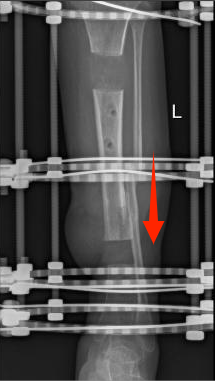

多年来,贵州航天医院各科室紧跟医学前沿,不断强技术、补短板,大力开展新技术、新项目,完成了许多高精尖、高难度、本地区“首例”的技术,填补了医院医疗技术空白,满足了群众日益增长的医疗需求。 贵州航天医院骨科率先在遵义地区开展骨搬移技术,截至目前,已治愈慢性骨髓炎、感染性骨不连、骨缺损、脉管炎、糖尿病足患者200余例,糖尿病足治疗保肢率达到98%。 本期,我们将为大家带来骨科特色技术——骨搬移技术(Ilizarov)。 案例分享 一名59岁的患者,身患糖尿病12年,在来我院3个月前出现了右脚溃烂的症状,来院就诊时,患者的右脚十分红肿,右脚脚趾坏死,伤口处不断流出黑红色脓液,情况十分严重。在接诊到患者时,骨科专家团队高度重视,立刻为患者完善了CT血管造影(CTA)等相关检查,诊断为:2型糖尿病,糖尿病周围血管病变,右糖尿病足。 术 前 考虑到患者情况比较严重,为最大限度保证患者肢体完整,科室专家团队进行了严格的讨论评估,为患者制定了骨搬移技术治疗方案,在征得患者及其家属的同意后,成功通过搬移骨块为患者进行治疗,促进患者病变肢体血管再生。 胫骨横向骨搬移外架固定 清除感染病灶 术后调节外架,通过搬移骨块 促进患肢血管再生 患者在术后三周前来换药,观察到感染得到进一步控制;术后六周复查,患者病变处已愈合,进行CT血管造影(CTA)后可明显观察到足部血管再生。 术后3周 术后6周愈合 CT血管造影见足部血管再生 糖尿病患者全身与局部的问题互为影响,形成恶性循环,糖尿病足溃疡创面迁延不愈,常见干性坏疽、湿性坏疽、趾坏死、深且大的溃疡以及骨髓炎等症状,还可导致脓毒血症,以往为保全生命,患者被迫选择一次或多次截肢。骨搬移技术的发展进步,能在血糖有效控制、局部有效清创下,有效促进患肢微血管再生,改善患肢血供,达到糖尿病足更快治疗康复的目的,并能根据病变情况最大限度的保障患者肢体完整。 什么是骨搬移技术 骨搬移技术是通过使用专用的骨外固定器固定骨段,每天缓慢牵拉,在牵拉搬移过程中,骨段尾部形成新骨及新的软组织,从而修复骨骼缺损及软组织缺损。是治疗大段骨缺损、骨不连、骨感染、肢体畸形的金标准方法,也用于治疗脉管炎、糖尿病足等肢体缺血性疾病。 骨感染缺损 切除感染段 搬移骨段 新骨形成 骨感染根治愈合 骨搬移技术原理 生物组织在持续、稳定、缓慢牵拉下,能刺激细胞分裂、组织再生,骨外固定技术运用该原理,通过持续缓慢调节外固定器形成牵拉张力,促进牵引成骨与相邻组织再生,如神经、血管、肌肉、皮肤等再生,达到治疗大段骨缺损、肢体缺血如糖尿病足等疾病的目的。 骨搬移技术优势 (一)除治疗骨缺损、骨不连外,有更广的适用范围,利用组织再生、血管再生等特性,能大量运用于肢体畸形的矫形、糖尿病足等的治疗。 (二)治疗效果确切,重建肢体外型和功能,极大降低截肢率和残疾率。 (三)明显提高了患者生活质量,极大减轻其家庭及社会负担。 肢体畸形的矫形 慢性骨髓炎 骨段切除 术后1年 濒临截肢的脉管炎术后6周 难愈创面术后3周 贵州航天医院骨科 专家团队 赵学平 骨科主任 主任医师 临床擅长:从事骨科临床工作30余年,对骨科常见疾病的诊治具有丰富的临床经验。 世界中医药联合会脊柱康复专业委员会常务理事,中华中医药学会整脊分会常务委员,中国中西医结合学会骨伤科分会肢体矫形功能重建与康复专家委员会常务委员,中国研究性医院学会骨科创新与转换专业委员会关节外科学组保髋工作委员会常委,中国康复技术转化及发展促进会骨外科与康复技术转化专业委员会常务委员,泛珠三角区域运动医学联盟(PPRD-SMA)理事会常务理事,中国研究型医院学会运动医学专业委员会委员,贵州省中医药学会整脊分会副主任委员,贵州省中西医结合学会银质针专业委员会副主任委员,贵州省康复医学会骨与关节专业委员会常务委员,贵州省人民医院骨科专科联盟常务理事,贵州省康复医学会骨内科专业委员会常务委员,中华医学会贵州省骨科学会委员,贵州省康复医学会脊柱脊髓专业委员会常务委员,贵州省运动医学分会委员,贵州省康复医学会骨与软组织肿瘤专业委员会委员,遵义市医学会创伤分会副主任委员,贵州省康复医学会骨内科专业委员会遵义地区分会常务委员,遵义市医疗事故鉴定、伤残鉴定、工伤鉴定、司法鉴定专家。 长期从事骨科临床研究及教学工作,在国家级、省部级杂志发表论文20余篇,SCI论文2篇,参与主编骨科专著2部,主持省部级科研项目2项,参与指导省部级、市级科研项目6项。 陈明勇 骨科副主任 副主任医师 临床擅长:从事创伤骨科工作约20年,对骨缺损、骨不连、骨肿瘤、肢体畸形等的肢体矫形重建及功能重建,慢性化脓性骨髓炎的根治治疗、糖尿病足的保肢治疗、快速康复理念(ERAS)下的老年骨折的诊治,四肢复杂骨折的诊治,四肢骨折等微创手术治疗具有丰富的临床经验。 2004年毕业于遵义医学院临床专业,曾在中国人民解放军总医院、广西医科大学第一附属医院、上海第六人民医院骨科进修。中国中西医结合学会骨伤科专业委员会横向骨搬移治疗糖尿病足及微血管网再生学组首届委员,遵义市医学会创伤分会常务委员。 瞿 辉 骨科 副主任医师 临床擅长:对骨科的常见病、关节外科、脊柱外科及运动医学疾病的诊治具有丰富的临床经验,熟练掌握骨科手术操作技术。 毕业于遵义医学院临床医学系,2005年前往广州中山大学第一附院骨显微医学部进修学习,2011年前往成都华西医院进修学习,并多次在省内外学习骨科相关知识,是中华医学会骨科分会会员。 赵兴东 骨科 主任医师 临床擅长:擅长骨科的常见病及各种创伤、四肢骨折创伤修复、骨感染、手足疾病的诊治和手足体表畸形的矫形整复,熟练掌握骨科四肢骨病及创伤的手术操作技术,尤其在四肢关节复杂性损伤、手足外伤、组织缺损创面、难治创面的皮瓣修复方面及平足、高弓足矫形方面及四肢慢性疼痛诊治、康复方面具有丰富的临床经验。 硕士研究生,毕业于遵义医学院临床外科系,2015年前往山东省立医院手足外科进修学习;遵义市医学分会创伤分会第一、二届委员,遵义市手外科医学会第二委届员会常务委员;在省级及省级以上期刊发表文章9篇,参编著作2部,参与主持并完成市级课题1项,参与市级课题2项、省级课题1项。 张俊凯 骨科 副主任医师 临床擅长:从事骨科临床工作28年,对创伤骨折、骨感染、骨缺损、骨不连等外科诊治,四肢骨折的微创手术治疗,四肢复杂骨折(如关节内粉碎性骨折、多发骨折等)的损伤控制及手术治疗等具有丰富的临床经验。 1995年毕业于遵义医学院临床专业,2009年前往复旦大学附属医院骨科进修1年。 卢懿明 骨科 副主任医师 临床擅长:从事骨科工作18年,对创伤骨折、四肢骨折的微创手术治疗、四肢复杂骨折(如关节内粉碎性骨折、多发骨折等)的损伤控制及手术治疗,尤其是髋部骨折的PFNA等微创技术,踝关节骨折、膝关节周围骨折的Mipo微创技术等具有丰富的临床经验,开展了4项新技术,发明6项新型专利技术。 2005年毕业于遵义医学院临床专业,2017年,前往南方医科大学第三附属医院骨科进修半年,回院后运用Mipo技术对骨干骨折及干骺端骨折的治疗技术,同时积极开展骨盆骨折、髋臼骨折腹直肌外侧切口的应用;发表了多篇专业论文,经常参与省内外学术交流会授课,获得医院荣誉称号多个。 邬夏荣 骨科 副主任医师 临床擅长:从事骨科工作16年,对四肢复杂骨折、骨肿瘤的诊治,尤其是足踝创伤、慢性踝关节损伤、平足症等诊疗具有丰富的临床经验。 2006年毕业于遵义医科大学临床医学专业,曾在陆军军医大学西南医院进修学习,发表多篇骨科学术论文。 余德怀 骨科 副主任医师 临床擅长:从事骨科工作10余年,对运动医学、骨关节、脊柱外科常见病、多发病的诊治具有丰富的临床经验。 硕士研究生,2011年毕业于遵义医学院临床医学专业,曾前往遵义医科大学附属医院运动医学专业进修学习;是贵州省医学会运动医学分会青年委员,西部关节镜联盟委员;发表多篇骨科学术论文。 冯 乾 骨科 副主任医师 临床擅长:从事骨科工作近20年,熟练掌握骨科多发病及常见病的诊治,尤其对脊柱退变性疾病的诊断及治疗具有丰富的临床经验,主要研究脊柱微创相关治疗方式,能熟练开展椎间孔镜及VBE。 曾前往北京大学第三医院进修学习疼痛及椎间孔镜、首都医科大学友谊医院专业进修脊柱内镜;是贵州省康复医学会第三届脊柱脊髓专业委员会委员;发明专利3项、发表脊柱外科专业论文多篇。 张艳金 骨科 副主任医师 临床擅长:从事骨外科工作16年,对复合伤、多发伤的救治、四肢骨干骨折、关节周围骨折、骨肿瘤、骨髓炎等诊治具有丰富的临床经验。 中共党员,硕士研究生,2006年本科毕业于山西医科大学第二临床医学院,2011年研究生毕业于北京军区总医院;在“老年COPD患者合并髋部骨折的诊治”国际合作课题组研究两年,在老年髋部骨折的诊治方面具有丰富的经验,并发表论文6篇;承担遵义市级课题1项;承担遵义医科大学的临床教学工作,获得遵义医科大学优秀带教老师荣誉。编撰有《骨科疾病诊疗精粹》一书,开展2项新技术,编撰地方规范《务川自治县创伤骨科常见疾病诊疗规范》一书。 赵小锋 骨科 副主任医师 临床擅长:从事骨科临床工作11年,对骨科常见病、多发病诊疗有较为丰富的临床经验,擅长脊柱相关疾病诊断及治疗,尤其是颈、腰、腿疼痛疾病诊断及治疗,擅长胸腰椎骨折微创经皮穿刺内固定术、经皮穿刺椎体成形术、经皮穿刺脊柱内镜下腰椎间盘摘除术、单纯开创腰椎间盘摘除术、腰椎滑脱复位椎间植骨椎融合内固定术、腰椎管狭窄减压融合内固定术及人工髋、膝关节置换术等。 2012年毕业于遵义医学院外科学专业硕士研究生,2019年参加“遵义市115医学人才精英计划”于上海交通大学第一附属医院培训学习,2023年于北京大学第三人民医院脊柱外科进修学习,曾获得遵义市优秀医师荣誉称号。 遵义市手外科第一届委员,遵义市医学会创伤分会第一届委员,遵义市医学会创伤分会第二届委员,贵州省康复医学会第三届脊柱脊髓专业会委员,遵义市医学会烧伤与整形外科学分会委员,发表论文5篇,其中国家级核心期刊1篇,SCI论文1篇,主持市级课题1项并结题,参与市级课题2项。 贵州航天医院骨科简介 基本情况 贵州航天医院(原3417医院)骨科组建于1968年,前身是以创伤和断肢(断指)再植闻名于世的上海市第六人民医院骨科,中国断肢(断指)再植的奠基者、中科院院士陈仲伟等著名专家、学者多次莅临科室指导医疗、教,是贵州省最早拥有专业骨科技术科室之一,在70年代开展了贵州省首例断肢(断指)再植手术。组建50余年来,诊治患者已逾百万,挽救了无数的伤病员,成为了保障遵义地区人民群众健康的重要支撑。 经过几代人的不懈努力,今天的骨科,已由创伤骨科发展至骨病、骨肿瘤、骨结核等领域,现有脊柱外科、关节外科、四肢创伤、手足外科四个亚专科,成为了集医疗、教学、科研于一体的综合学科,是贵州省临床重点专科、遵义市临床重点专科、遵义市骨科临床医学中心、遵义市基层骨科专科联盟理事长单位。 科室目前开放床位110张,共有医护人员50余人,副高级以上专家18人,硕士研究生15人。拥有一流骨科医疗设备多台,每年不定期选派优秀技术骨干到全国各大知名医学院校进修、学习、参观、交流,并邀请国内、国外知名专家教授来院进行交流、指导,通过不断引进国内外先进的诊疗技术,科室医疗技术水平稳步提升,为广大人民群众提供了优质的医疗服务。 专科特色 骨一科 (一)骨缺损、骨不连的肢体与功能重建 胫骨横向骨搬移技术治疗糖尿病足: (二)慢性骨髓炎的根治治疗 (三)肢体缺血性疾病如糖尿病足、脉管炎的保肢治疗 (四)皮瓣修复 (五)复杂创伤的治疗 (六)老年髋部骨折及小儿骨折快速手术 老年髋部骨折: 骨二科 (一)胸腰椎骨折微创经皮椎弓根螺钉固定术 (二)老年性骨质疏松性患者腰椎滑脱脊柱内固定术(骨水泥螺钉) (三)V形双通道脊柱内镜技术(VBE)腰椎融合术治疗腰椎退行性疾病 (四)老年性骨质疏松性骨折(PVP/PKP)术 (五)人工髋关节置换术 (六)双侧股骨头坏死人工全髋关节置换 (七)右侧全髋置换术后假体周围骨折翻修 (八)人工膝关节置换术 (九)人工膝关节假体松动翻修 (十)关节镜技术 传统手术切口 关节镜技术切口 诊疗范围 骨一科 1.四肢创伤、矫形。 2.手、足踝外科。 骨二科